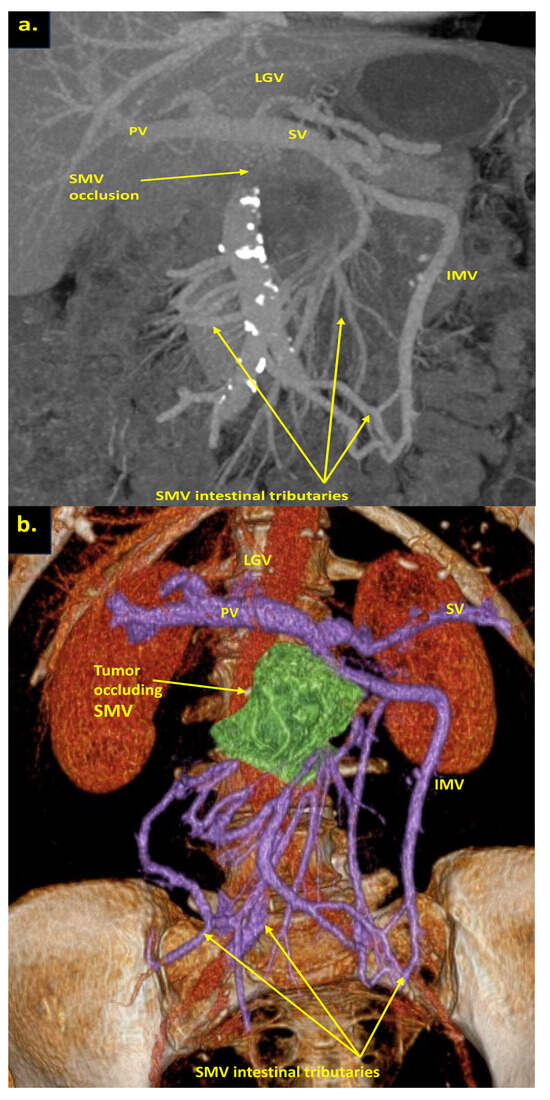

Pancreatoduodenectomy with the SMV and all its tributaries resection without reconstruction for the uncinate PDAC in 64-year-old male. On CT the tumor invades the SMV, which is occluded, the SMV-SV confluence is preserved, and the IMV collaterals are well-developed with dilated intestinal veins, without right-sided vein collaterals and varices. (a) Three-dimensional MIP and (b) three-dimensional VR reconstructions show the dilated SMV tributaries, gastro-epiploic venous arcade, and IMV flowing into the SV; (c) the picture of the operating field after the extended Whipple procedure with the SMV and all its tributaries resection without reconstruction. CHA—common hepatic artery, IVC—inferior vena cava.

Figure 6.

Total pancreatectomy with the SMV and all its tributaries resection with resection of IMV and its transposition into SV stump, combined with SMA resection and reconstruction for the uncinate PDAC in 71-year-old female. On CT the tumor invades the IMV and SMV (the last one is occluded), the SMV-SV confluence is preserved, and the IMV collaterals are well-developed with dilated intestinal veins, without right-sided vein collaterals and varices. (a) Three-dimensional MIP and (b) three-dimensional VR reconstructions show the dilated intestinal veins flowing into the IMV, which connects to the SV; (c) the picture of the operating field after the extended Whipple procedure with the SMV and all its tributaries resection without reconstruction. CHA—common hepatic, LGA—left gastric, SA—splenic, RHA—right hepatic, LHA—left hepatic, SMA—superior mesenteric arteries, CA—celiac artery, IVC—inferior vena cava.

In this study, only cases with full excision of SMV trunk and resection of all its tributaries, namely middle and right colic veins, ileocolic trunk, and all the first-order SMV branches (jejunal and ileal), without the reconstruction of above-mentioned vessels, were included. The usual length of the resected SMV with the branches in these cases was 7–8 cm (Figure 5 and Figure 7).

We used different post-processing CT techniques for the assessment of the peripancreatic vessels and collateral venous blood flow adequacy, such as shaded surface display, maximum intensity projection, and 3D volume-rendered (VR) reconstruction imaging. Now, when planning SMV resection with excision of all its tributaries for “low” pancreatic cancer, we consider CT-based 3D-VR reconstruction the best and most necessary option for the depiction of the collateral venous system. Compared to the other rendering CT techniques, VR is superior in delineating vessels, pancreatic parenchyma, the tumor, and adjacent structures (Figure 1a–d, Figure 5a,b, Figure 6a,b and Figure 7a,b,d) [43,44,45].